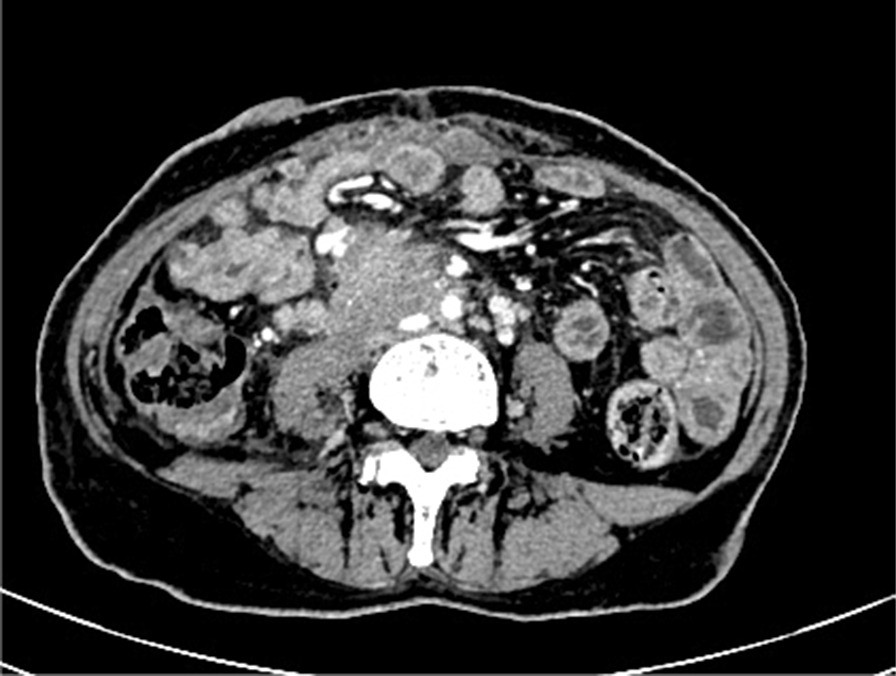

Fig. 7From: Ureteral urothelial carcinoma with squamous cell carcinoma and sarcomatoid carcinoma differentiation: a case reportTumour invades and wraps right iliac blood vesselBack to article page